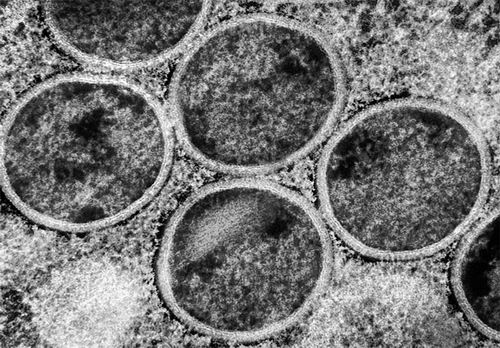

猴痘病毒似乎更容易在人与人之间传播。图片来源:NIAID/SPL

猴痘可导致出现疼痛、皮肤病变和发热,严重时会致死。已知猴痘病毒分为4个亚型:Ⅰa、Ⅰb、Ⅱa和Ⅱb。